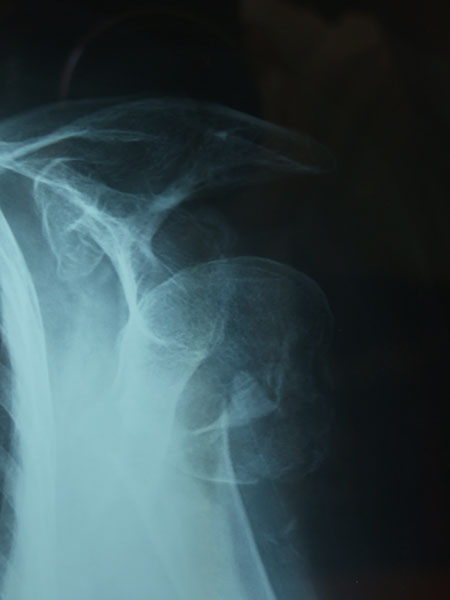

Fractura impactada de húmero .

Fractura de húmero, intensa desviación de fragmentos

Fractura compleja de húmero.